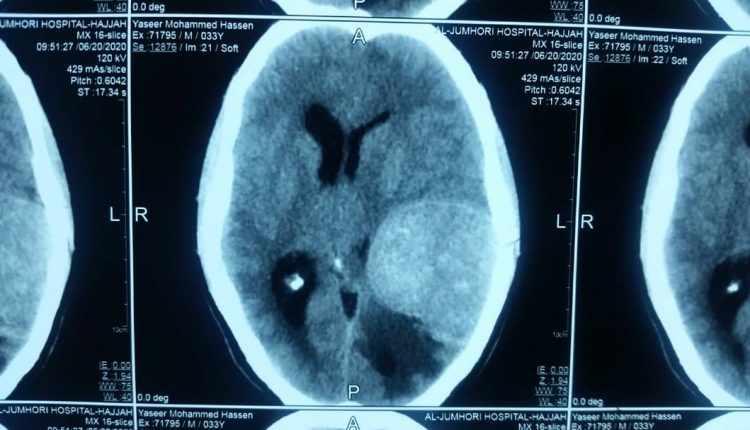

تمكن فريق طبي بهيئة المستشفى الجمهوري بحجة من إزالة ورم دماغي من مريض يبلغ من العمر 32 عاماً.

فيما أشار رئيس الفريق الطبي – أخصائي جراحة المخ والأعصاب والعمود الفقري الدكتور علي جعفر إلى أن المريض كان يعاني من صداع شديد وضعف في اليد اليمنى.

وذكر أنه تم تشخيص حالة المريض وإجراء الفحوصات والأشعة المقطعية اللازمة لمعرفة حجم الورم ومكانه قبل إجراء العملية الجراحية التي تمت بنجاح.